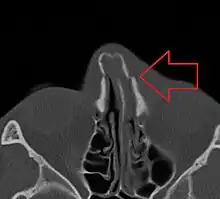

Bilateral nasal fracture as seen on CT scan

Minor nasal fractures may be allowed to heal on their own provided there is not significant deformity. Ice and pain medication may be prescribed to ease discomfort during healing.[1] For fractures where the nose has been deformed, manual alignment may be attempted, usually with good results. A CT scan of the facial bones is recommended before this occur.[4] The reduction can take place within the next two weeks and potentially up to 5 weeks; though repair is recommended earlier in children (around 7 days).[4]